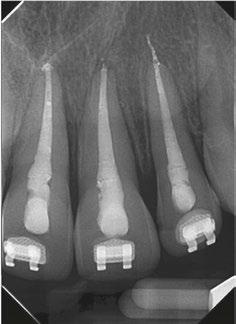

There are various factors that influence the size of such cavities, notably the anatomical location of the orifices and visualizing these orifices without tilting the mirror.12 This results in an access cavity that is widest occlusally and smallest at the level of the orifices.12,13 Hence the drawback of such access cavity design is that it requires the removal of healthy tooth structure, specifically the pericervical dentin — the dentin present 4 mm above and 6 mm below the crestal bone which helps to distribute any forces placed on the tooth (Figure 1).14 This access design, known as Traditional Endodontic Cavity (TEC) is presently being questioned, giving rise to various access designs emphasizing the preservation of this pericervical dentin.14,15

Conservative Endodontic Cavity (Figure

2A)

The Conservative Endodontic Cavity (CEC) is a first step towards a less invasive access cavity while executing a root canal treatment. It is based on the partial deroofing of the pulpal chamber while preserving pulpal horns, resulting in a slight occlusal convergence. This elimination of straight-line access makes orifices visible one at a time using different visual angulation.16